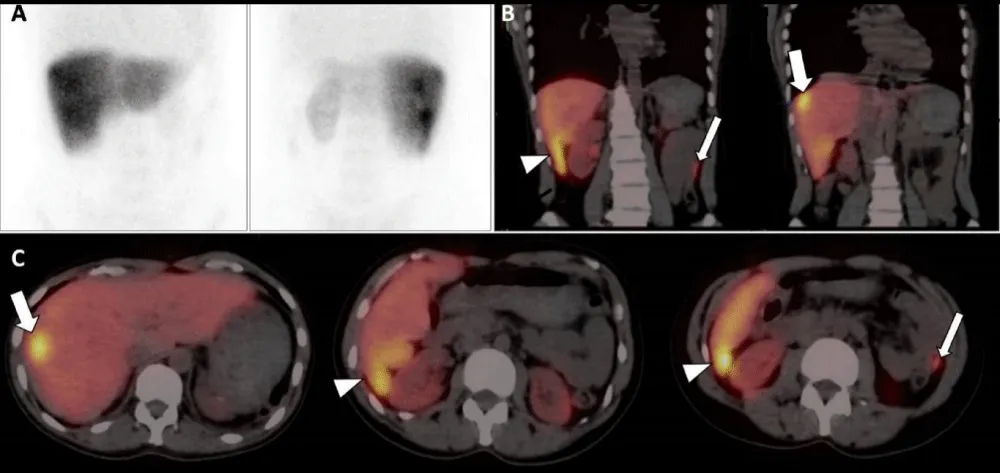

A 41-year-old woman with a history of abdominal pain was referred to ultrasonography (US). US was negative and computerized tomography (CT) was performed for further investigation. CT images disclosed the absent of spleen and a well-defined hypodense lesion compared to the liver, located near the liver capsule with a maximum diameter of 22 mm in the segment 8. In addition, multiple nodular formations were seen near the segment 6 of the liver. During the portal phase, the lesions were hyperdens compared to the liver. On MRI imaging, the lesions were hypointense on T1-weighted images and hyperintense on T2-weighted images. After contrast media administration (Gd+), all lesions showed heterogeneous contrast enhancement on the arterial phase, and homogeneous enhancement on the portal phase images (Figure 1). Peritoneal carcinomatosis was suspected but the patient had no complaints of fever, night sweats or weight loss, which suggests malignancy. Her history included splenectomy 20 years previously due to the traumatic rupture of the spleen during an accident. She went on to have 99mTc-labeled heat-damaged red blood cell (RBC) scintigraphy because of prior splenectomy. One gr of stannous ion (Sn+2) in the form of pyrophosphate was injected intravenously to the patient. 20 min later, a blood sample (approximately 8 cc) was obtained, 20 mCi of NaTc99mO4 was added, the sample was incubated at room temperature for 20 min then the sample was re-injected to the patient. Planar and hybrid single photon emission tomography/computed tomography images (SPECT/CT) were obtained. Planar images showed suspicious visual moderate activity uptake in the right upper quadrant and mild activity uptake in the left upper quadrant of the abdomen (Figure 2A). Hybrid SPECT/CT images provided the accurate localisation of the lesions in the liver (Figure 2B,C, thick arrow) and the other mesenteric and peritoneal ones (in the Morrison’s pouch and left paracolic gutter - Figure 2B,C, arrow head and thin arrow, respectively). These lesions were unchanged for ≥ 5 months compared to prior exams and did not demonstrate any changes in a second MRI session which performed 5 months later. The diagnosis of intrahepatic and peritoneal splenosis was confirmed without invasive diagnostic techniques.